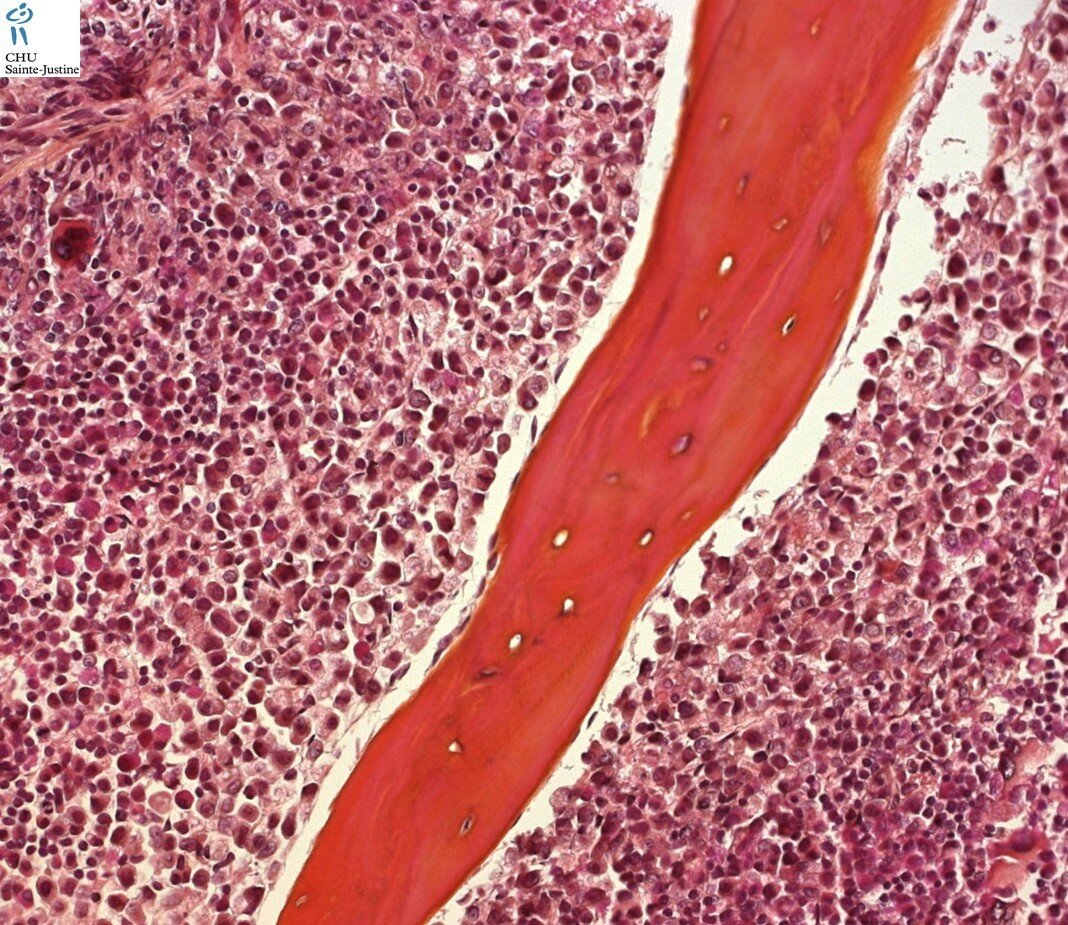

Morphology